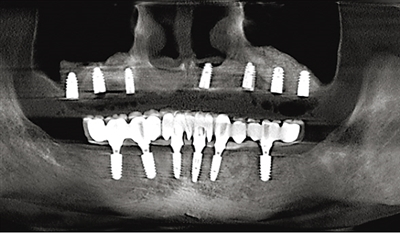

兰院长给出的种牙方案是,在植骨同时植入5颗种植体,支撑半口牙桥完成修复。这样设计能使骨生长与骨愈合同步进行,不但有效缩短治疗周期,还能让种植体与牙槽骨的结合更为牢固。仅用了3个月,吴伯就重新拥有了一口新牙:“现在吃饭就像用自己的牙齿一样舒适,植骨也值得!”